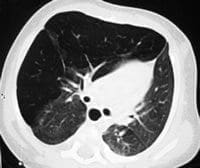

Figuras 2 A, B, C y D. TCAR en inspiración (izquierda) y espiración (derecha). Sobreinsuflación del lóbulo superior derecho

con hipovascularidad y desplazamiento contralateral de las estructuras mediastinales.

En los cortes en espiración las alteraciones descritas son más evidentes.